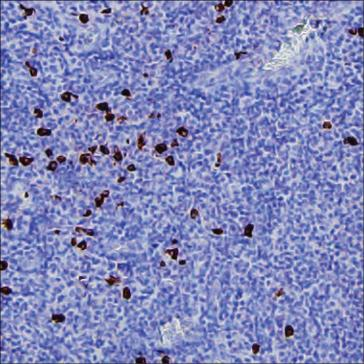

| IHC | 1/500-1/1000 | Human,Mouse,Rat |